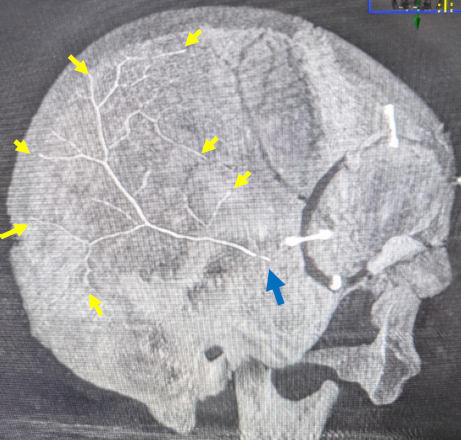

Next-Generation Liquid Embolic, NeoCastTM, Successfully Occludes Distal Middle Meningeal Artery Branches of Chronic Subdural Hematoma Patients in Initial Cohort of First-In-Human Study

Abstract Body: Introduction: NeoCast is a novel, solvent-free, non-adhesive, shear-thinning, liquid embolic agent designed to reproducibly achieve distal penetration of the microvasculature. In preclinical models NeoCast showed deeper and more consistent distal penetration relative to commercial benchmarks. These properties were confirmed in the EMBO-01 clinical study which demonstrated initial safety, excellent embolic performance, and extensive tumor devascularization in patients with hypervascular extra-axial tumors. Here, we report on the first use of NeoCast for MMA embolization in an initial cohort of patients with chronic subdural hematomas (cSDH) from the EMBO-02 study.

Results: An initial cohort of patients (age range: 55-80 years old) was enrolled in EMBO-02 including one patient presenting with a bilateral hematoma. All target MMA vessels were successfully embolized with NeoCast (volume injected: average 0.22ml, range 0.06-0.43ml) resulting in complete occlusion with no non-target embolization. Injection occurred in both flow-directed (placed proximal to bifurcation) and wedge position (selected distal branch) scenarios. In both scenarios, deep distal penetration was achieved with embolic reaching the falx. The investigator was satisfied to very satisfied with NeoCast’s overall embolization performance as graded on the usability questionnaire. No device-related serious adverse events have been reported to date.